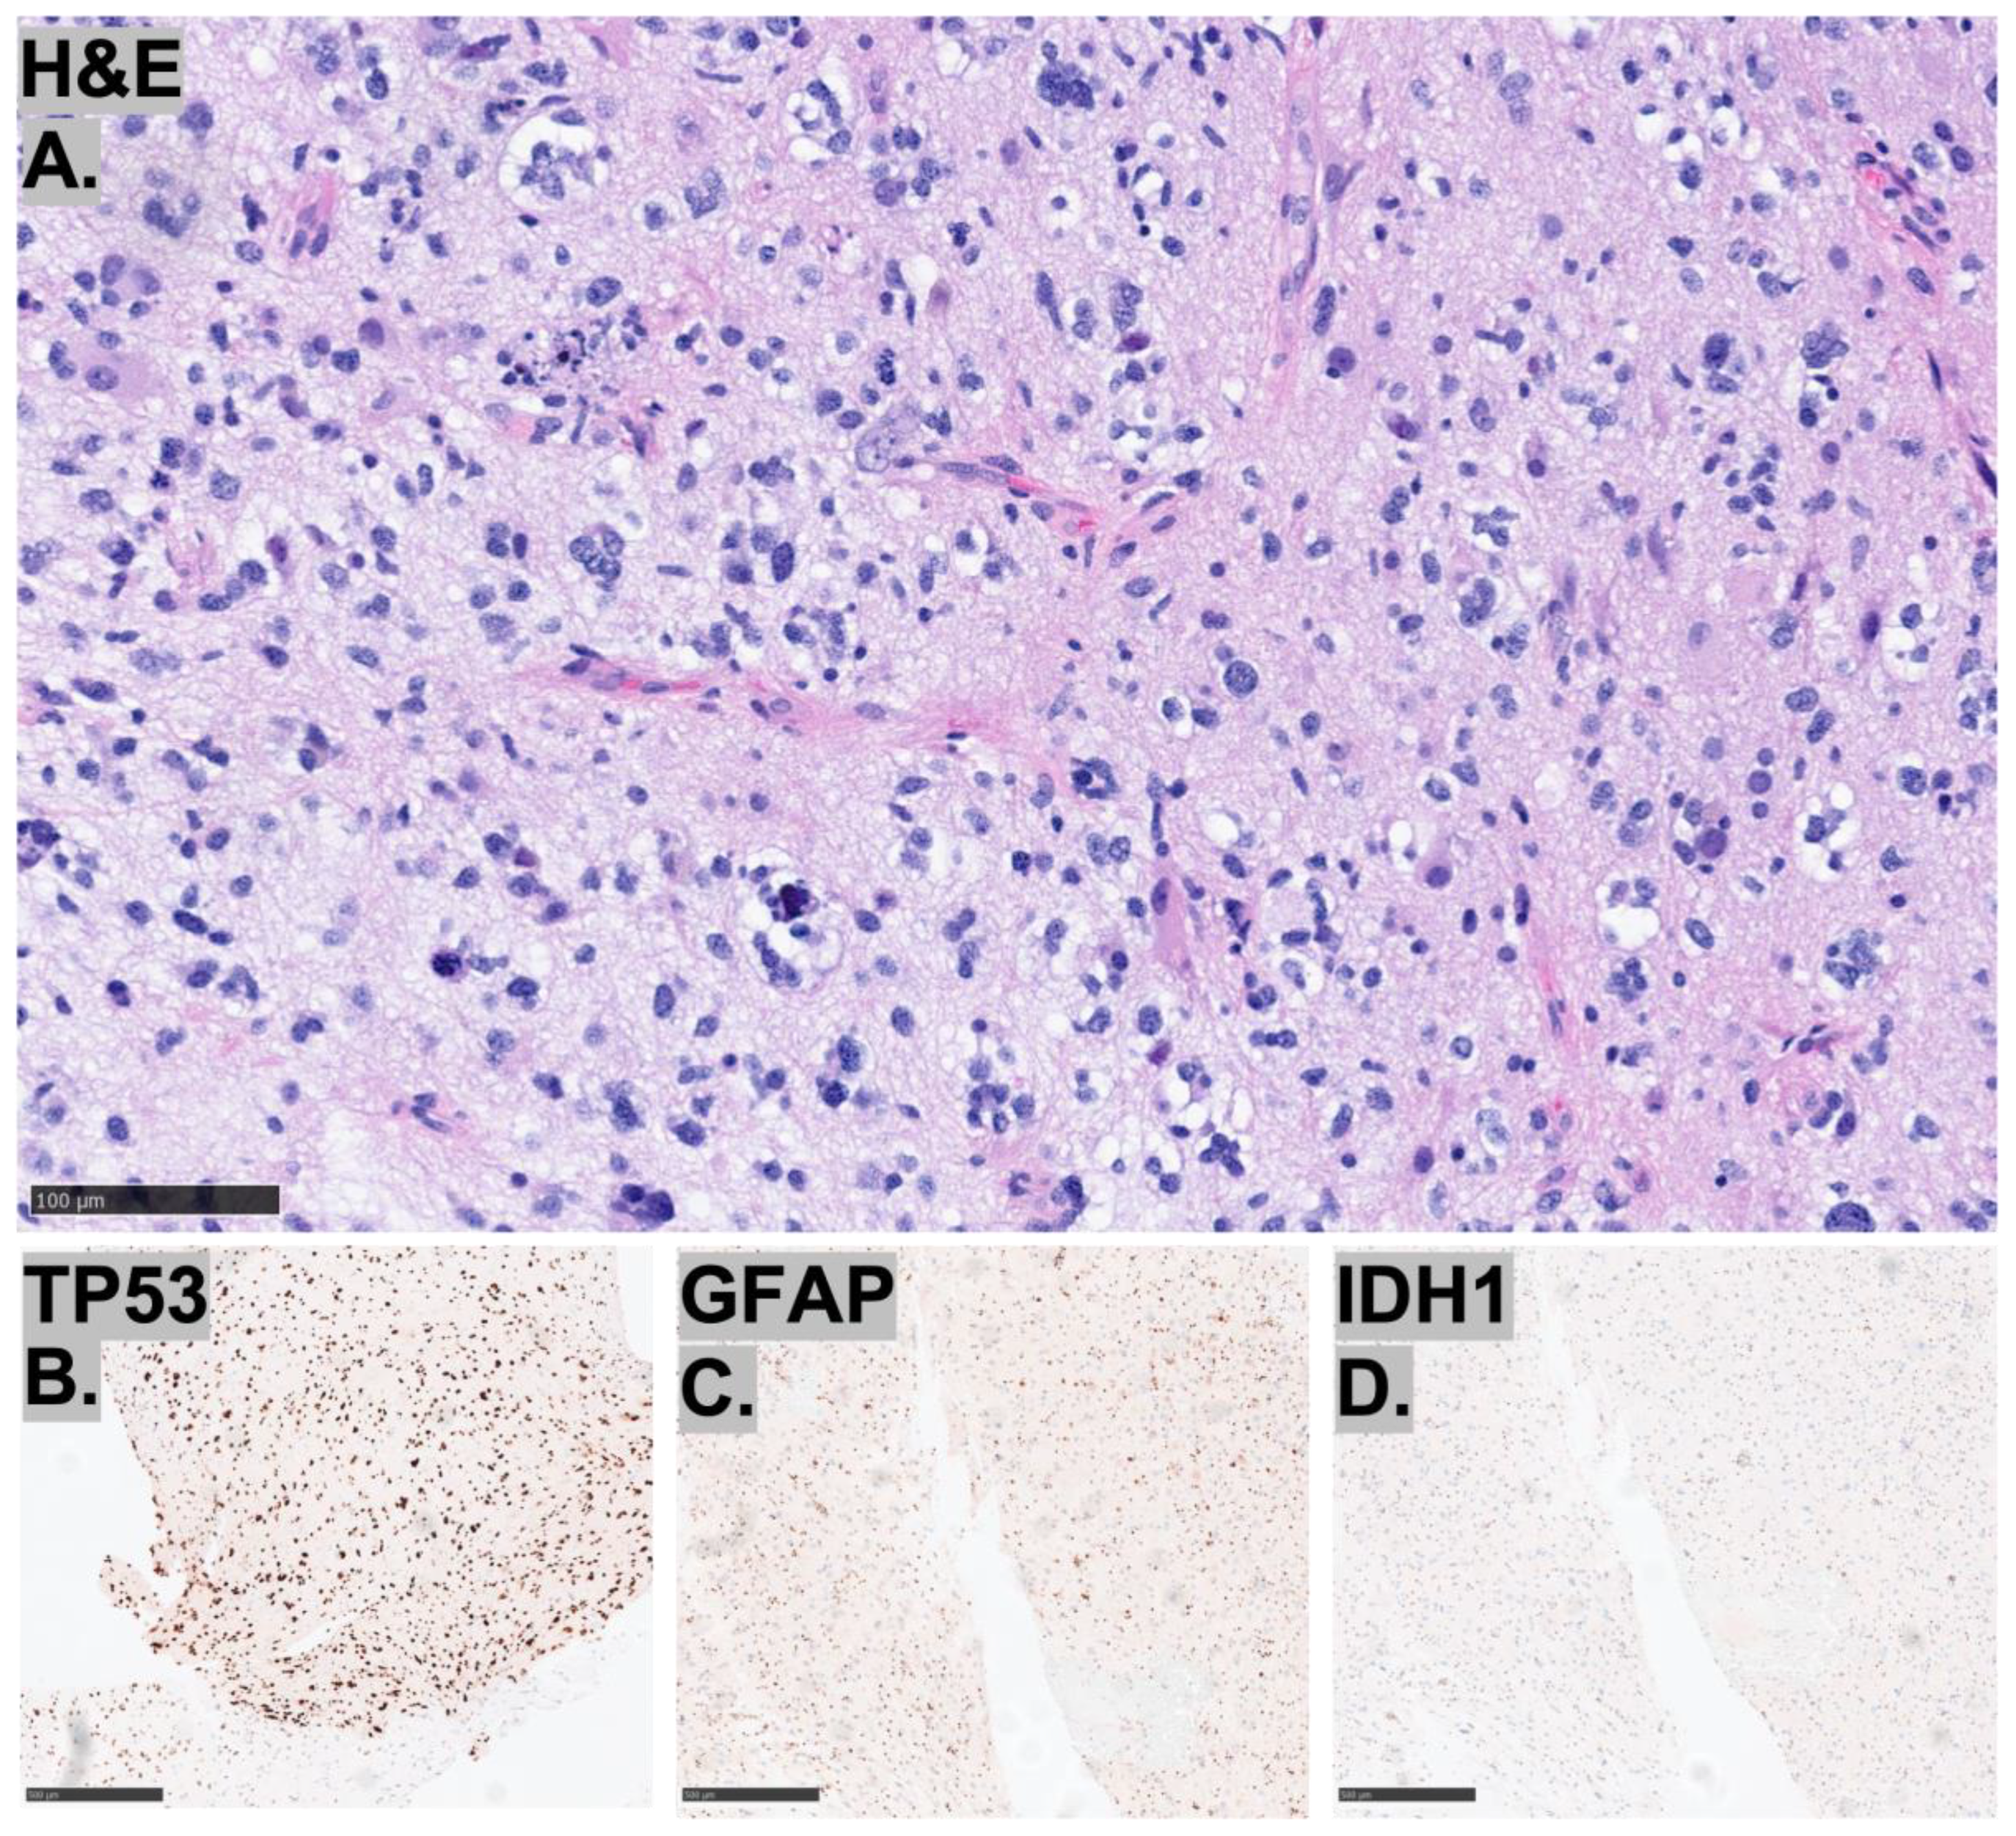

2.3. Histopathological Characteristics of the Tumors

2.4. Molecular Characteristics of the Tumors

| Histopathology | Case 1 | Case 2 | Case 3 |

|---|---|---|---|

| ATRX | + | + | + |

| p53 | overexpression | overexpression | overexpression |

| Ki-67 index | elevated | elevated | elevated |

| IDH1 | − | − | − |

| GFAP | + | + | + |

| Synaptophysin | weakly positive | ||

| Olig2 | − | patchy positivity | + |

| BRAF V600E | − | − | |

| H3K27M | − |

| Molecular | Case 1 | Case 2 | Case 3 |

|---|---|---|---|

| IDH1/2 | − | − | − |

| TP53 | Normal | Pathologic mutation | Pathologic mutation |

| ATRX | − | − | − |

| BRAF | − | − | − |

| CDKN2A | − | − | − |

| CTNNB1 | − | − | |

| EGFR | − | − | − |

| FGFR1/2/3 | − | − | − |

| HF3A | − | − | − |

| HIST1H3B | − | − | − |

| MET | − | − | |

| PDGFRA | Variant | − | Pathologic mutation |

| PTEN | − | − | |

| PTPN11 | − | − | |

| TERT | − | − | − |

| GNA11 | Variant | ||

| PPM1D | Variant | ||

| MGMT promoter methylation | + | − | + |

| Gene fusion events | − | − | − |

| Chromosomal microarray | Near-haploid/pseudohyperdiploid genome with gain of chromosome 7 and copy neutral loss of heterozygosity of chromosome 10. | Chromosome copy number complexity with chromothripsis of chromosome 2, loss of 7p22.3p21.3, loss of 9p, loss of 11p, loss of chromosome 12, loss of 13q11q12.11, loss of 13q14.11q14.3 (including RB1), loss of 13q21.31q21.32, loss of 14q12q32.33, loss of 17p13.3p11.2 (including TP53), multiple level gain of 17q, and loss of 19q13.43. | Loss of chromosomes 2 and 5, loss of 9p24.3p21.1 (including CDKN2A and CDKN2B), and gain of chromosome 17. |